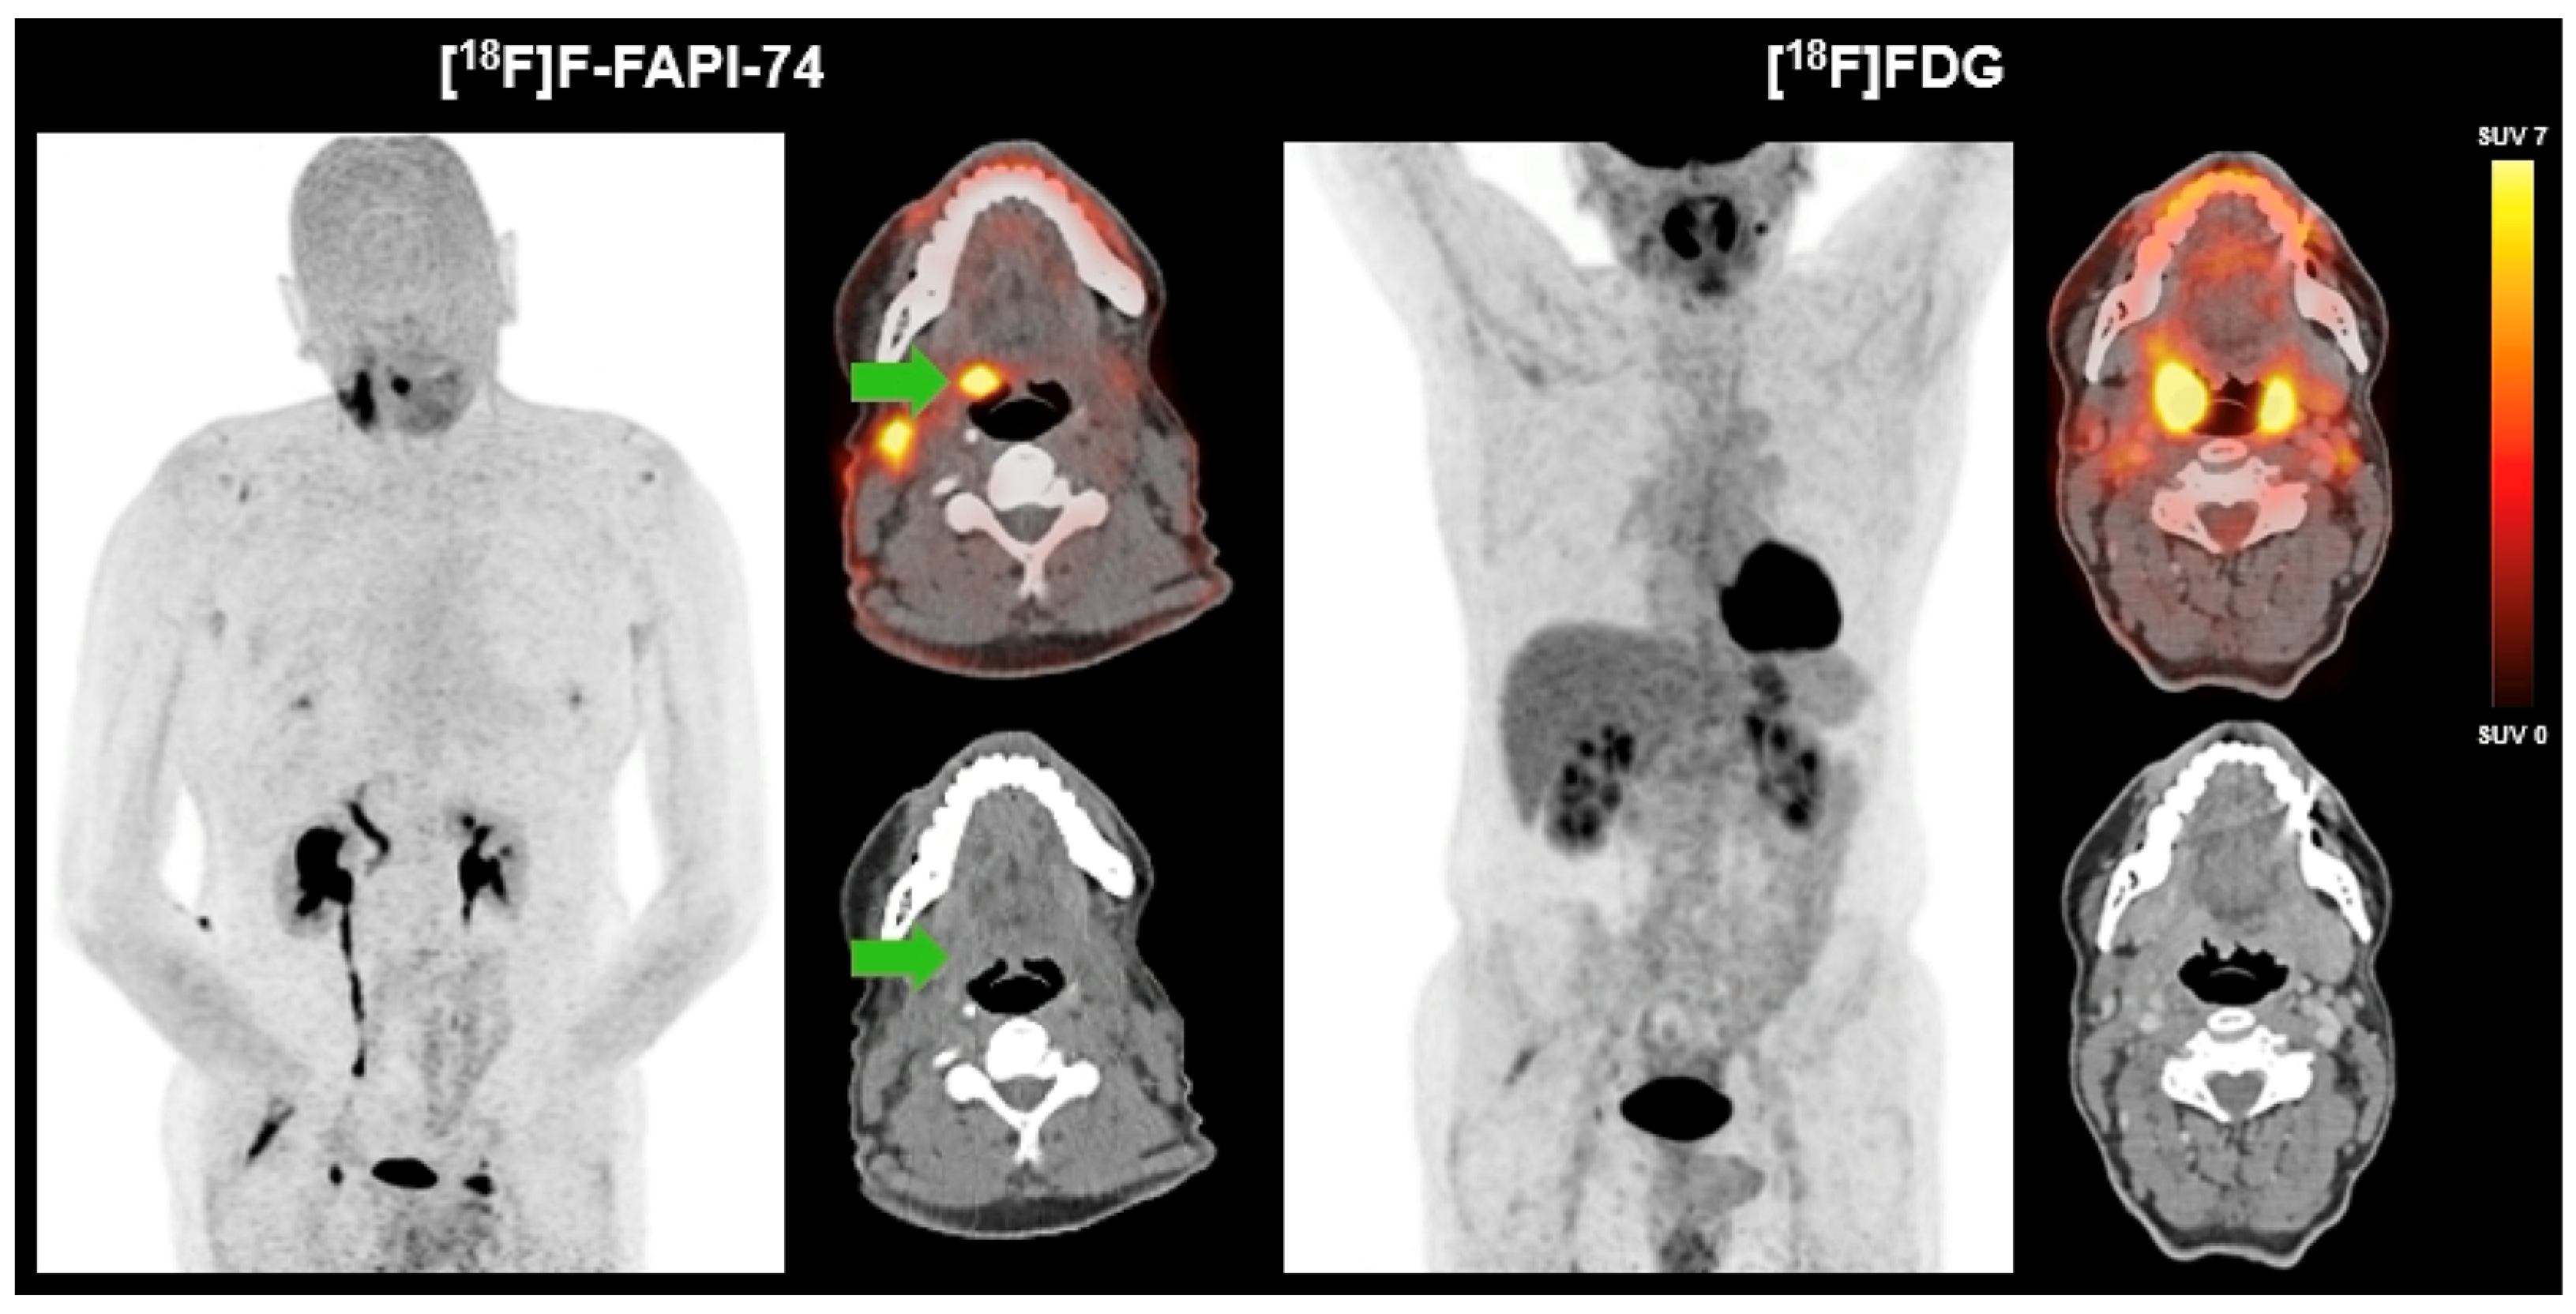

3.2. Case Study